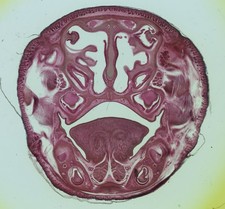

Magic Lantern Slide SECTION OF

#sponsored

Magic lantern slide section - magic, - €15.00

Add to cart See photo - Free postage - New and Used